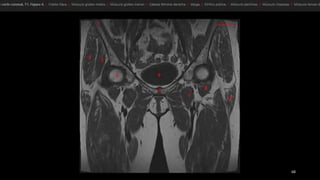

• tensor de la fascia lata (tfi), el psoasilíaco

(Ips), el sartorio (sa) y el recto femoral (rf).

• los vientres musculares se representan en

gris y los tendones, en negro.

• Punta de flecha blanca señala el tendón del

recto femoral.

• flecha, fascia lata.

• músculos pectíneo

(Pt), aductor largo (1),

aductor corto (2),

aductor mayor (3) y

recto interno (Gr).

• ObtE, obturador

externo

• músculo glúteo mayor (GMa)

• músculo tensor de la fascia lata (Tfl anterior y la

fascia lata (FL) situada entre ambos músculos

• «bandeleta de Massiat» (BM)

• glúteo medio (GMe) y glúteo menor (GMI)

• trocánter mayor (TM)

• El músculo glúteo mayor (GMa).

• músculos semimembranoso (sm), semitendinoso (st)

y la cabeza larga del bíceps femoral (elb).

• músculo semimembranoso tiene su propio tendón

(1).

• semitendinoso y la cabeza larga del bíceps se originan

en la cara lateral de la tuberosidad isquiática -en un

tendón común (2).

• nervio ciático (NC). TM, trocánter mayor.